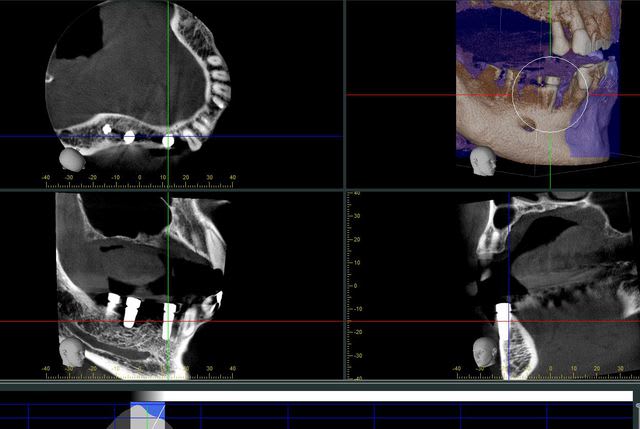

voici deux images traitées avec simplant d'un même patient la première est faite avec un Planmeca et la seconde avec Vatech

à vos commentaires...

peu importe, l'image vatech est sensiblement plus floue que planmeca, j'ai pu le constater plusieurs fois.

ici, je profite d'avoir le même patient pour montrer la différence que je vois à chaque fois.